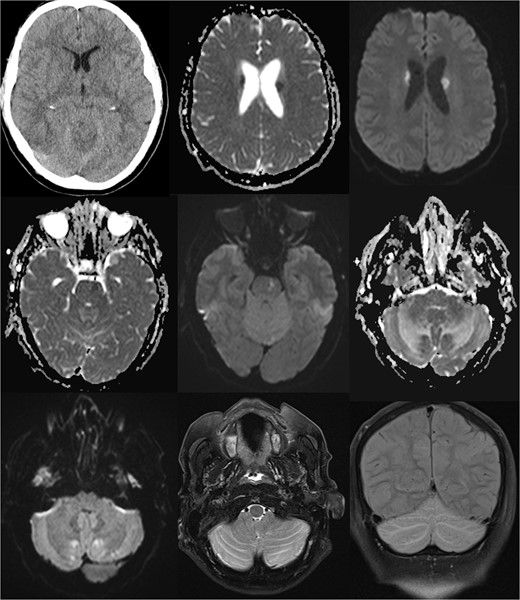

A 61-year-old male was electively admitted for surgical management of adjacent segment instability in the lumbar level L2/3 after fusion of the segments L3-S1 in the past. The surgical procedure proceeded intra-operatively without complications. However, rapid vigilance reduction was noted in the recovery room. Initial assessments ruled out opioid overdose and non-convulsive seizure with the administration of Naloxone and benzodiazepines, leaving the cause of reduced vigilance unclear. Protective intubation was performed in the recovery room, and cranial CT (cCT) scans revealed effaced sulcal relief and hypodense basal ganglia, suggesting the onset of hypoxic brain damage (as seen in Fig. 1).

Comprehensive computer tomographic (CT) and magnetic resonance imaging (MRI) of pseudohypoxia brain damage due to CSF loss; from left to right, top to bottom: (1) CT axial view showing general brain structure and pathology; (2 + 3) diffusion-weighted imaging (DWI) and apparent diffusion coefficient (ADC) maps of the basal ganglia, and (4 + 5) DWI and ADC images of the pons; (6 + 7) DWI and ADC images of the cerebellum; (8) T2 Turbo Spin Echo with fat saturation (TSE FS) axial view of the cerebellum; (9) Sagittal T2 turbo inversion recovery magnitude coronal view depicting tonsillar descent with cerebellar edema, and these images illustrate the intricate brain changes associated with pseudohypoxia damage following CSF leakage.

The patient was admitted to the intensive care unit, cardiopulmonary stable but without awakening response after sedation cessation. Cranial MRI revealed basal subarachnoid hemorrhage, significant cerebellar vasogenic edema, swelling of the posterior cranial fossa, tonsillar descent, and ventricular compression, indicative of pseudohypoxic brain swelling due to CSF loss (as seen in Fig. 1). The surgical drainages were delivering no signs of CSF loss. An external ventricular drain (EVD) was placed for brain pressure compensation showing a clear appearing CSF with an opening pressure over 20 mmHg. A conservative intracranial pressure therapy with mannitol and deepening of sedation was initiated. Subsequent CT imaging showed progressing global brain edema and cerebellar and basal ganglia infarcts. The following cranial and spinal MR Imaging showed an extensive CSF leakage with wide epidural spread, necessitating revision surgery to cover a 4-mm dural tear at the lumbar level L2/3 by stitching over the dura and applying a Tachosil sponge (as seen in Fig. 2).